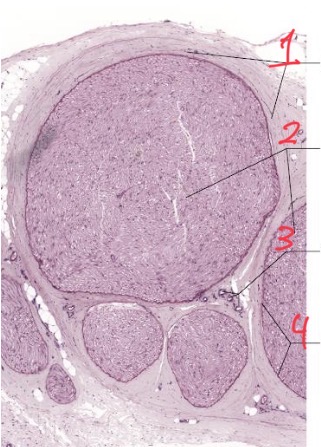

1

Schwann cell

2

Myelin sheath

3

Axon

4

Perineurium